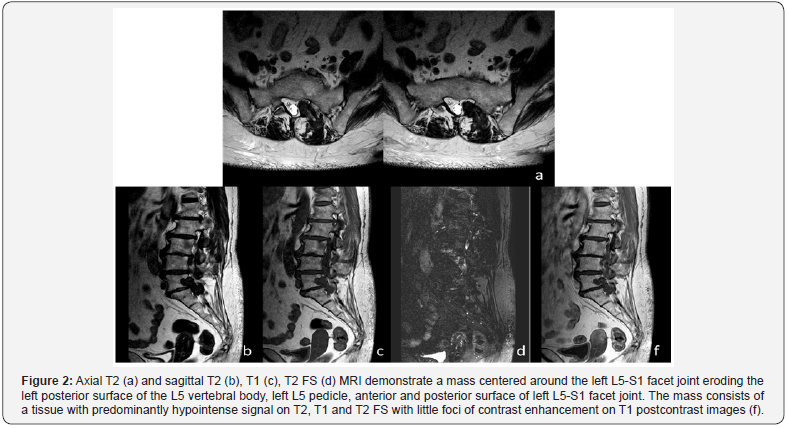

CT and MRI images (Figures 1 & 2) demonstrate a heterogeneous mass centered on left L5-S1 facet joint with epidural extension and posterior paraspinal component. CT images show a few faint punctuate calcifications within a predominantly non-calcified mass causing chronic smooth erosion of left posterior cortex of the L5 vertebral body, left L5 pedicle, anterior and posterior surface of left L5-S1 facet joint. On MRI the mass consists of a tissue with predominantly dark signal on T1, T2 and T2 FS sequences with little foci of contrast enhancement. The epidural component of the mass spreads along the left anterior wall of the spinal canal, compresses the left S1 nerve root within the neural foramen. The posterior paraspinal component pushes back the left multifidus and longissimus thoracis muscle. The patient underwent the surgical removal of the tumor with osteoplasty of bone defect at the N.N. Blokhin National Medical Cancer Center.